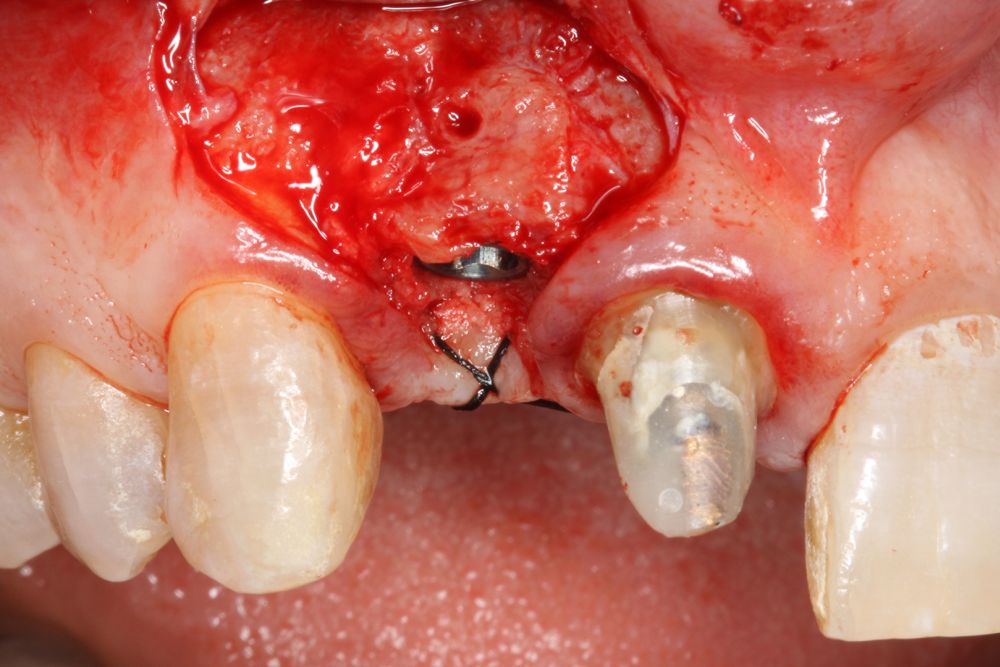

We present the case of a 36-year-old woman who comes to the clinic demanding solution for an implant located in position 1.2. This implant has carried a rehabilitation with a crown for a short period of time in which an important mucositis and loss of the thickness of the gingival tissue occurred, for which the crown was removed. The patient has a provisional removable crown and the soft tissue surrounding the area of the initial emergency of the implant-supported prosthesis is in bad condition, with a significant loss of thickness and the remains of a soft tissue fistula (Figures 1-4).

To continue with the study of the case, a Cone Beam is performed where we can observe three-dimensionally the position of the implant located in position 1.2. In the sectional cuts it is visualized completely positioned toward vestibular with an almost complete resorption of the cortical bone of this area, which explains the underlying soft tissue problems. The periapical radiography shows the position of the implant with respect to adjacent teeth (Figures 5 and 6). With this image we proceed to create a flap and the explantation of the implant. The crown located in tooth 1.1 is also removed to be able to make another crown that will serve to support the provisional extension for zone 1.2, while the first procedure heals. In this first approach a block grafting obtained from the mandibular ramus is also placed which is fixed with a microscrew in the area to be regenerated where the vestibular cortical has been lost. Once fixed and positioned, it is filled around the block grafting with particulate bone obtained with a bone-scraper of the same donor zone embedded in PRGF-Endoret for better fixation and cellular viability (Figures 7-9).